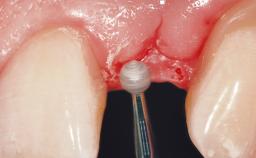

A 30-year-old female patient was referred to the office for the treatment of tooth 11. Her chief concern at the initial visit was to inquire, “Why is my tooth pink?” Upon clinical examination, it was determined that tooth 11 had a previous history of trauma and that the clinical crown had become noticeably pink in color as a result of internal resorption. This diagnosis was confirmed radiographically, indicating a large radiolucency involving the central and distal portions of the clinical crown. It was determined that restoration of this tooth was not possible, and that extraction was indicated. The presence of a mid-line diastema, which the patient wanted to reproduce, directed the treatment plan for tooth replacement utilizing a dental implant.

Soft Tissue Grafting None

Soft Tissue Contour and Volume Ideal